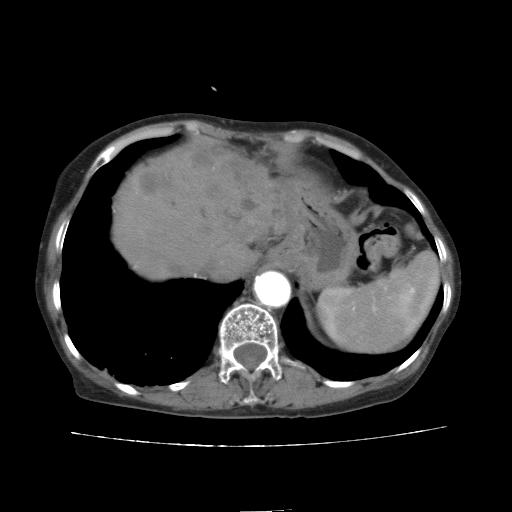

延迟期

看片子胆管里结石,肝上显示的占位会不会是胆管癌?大家帮忙看看,图像不太好,手头的处理文件没有,大致转换了一下,有原始图像数据

胆管细胞癌,胃壁增厚

支持胆管细胞癌诊断,胃壁增厚。